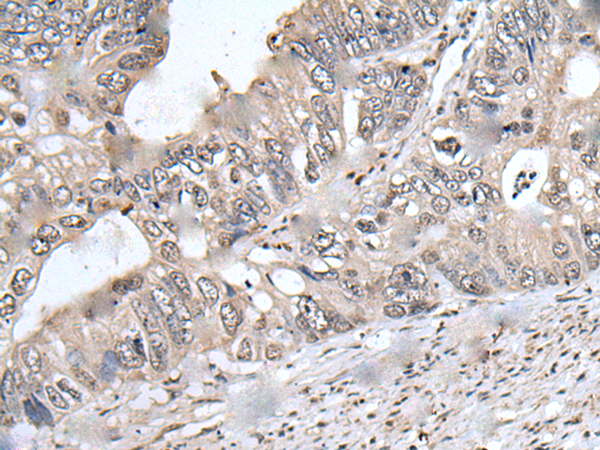

分类: 科研抗体货号: P08628别名: SAK; STK18; MCCRP2应用: IHC反应种属: Human, Mouse, Rat